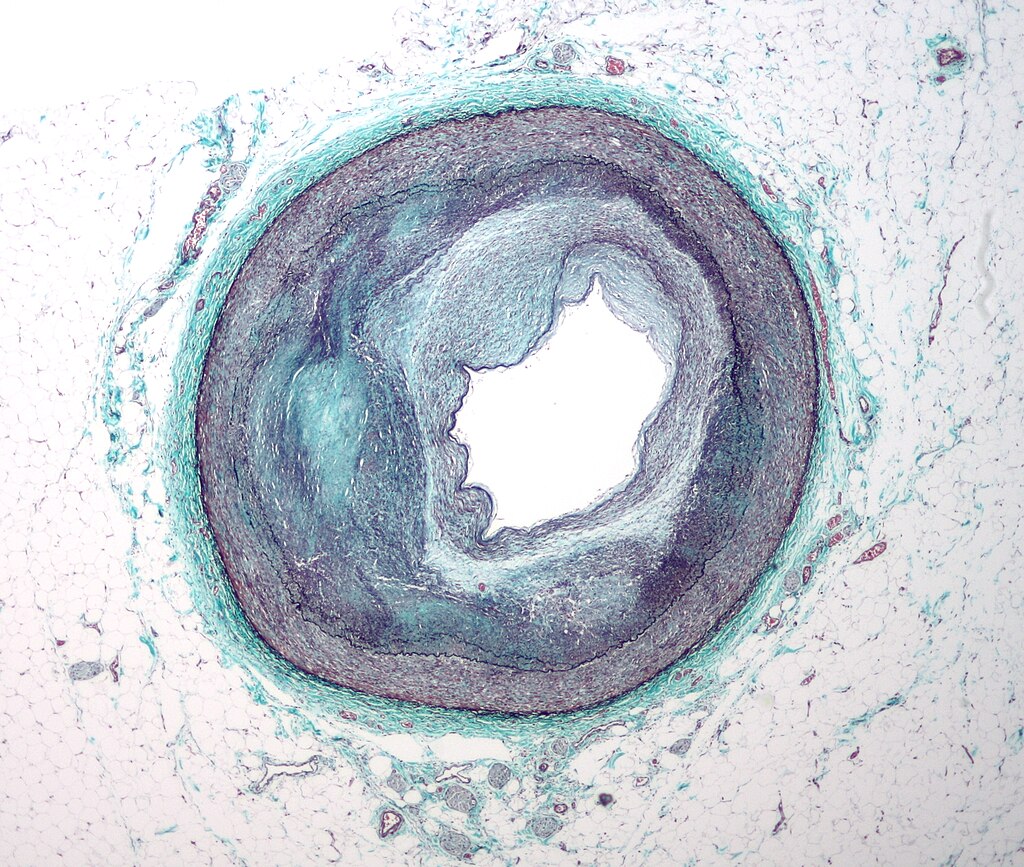

Mikrofotografia tepny zásobujúcej srdce  s významnou aterosklerózou. Viditeľné je výrazné zúženie lúmenu. Tkanivo bolo obarvené Massonovým trichromom. Kredit: Nephron, Wikipedia, CC BY-SA 3.0